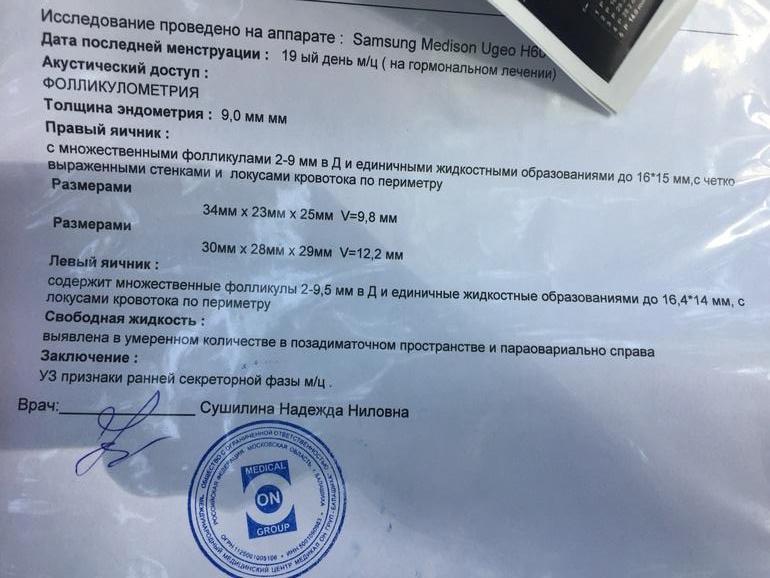

А вообще вот что)

Вот теперь сижу, гадаю...) жду протокол)) по сути.. от укола 10000 фолликулы же не могли остановиться/уменьшиться.. они либо в кисту бы уже ушли, либо лопнули. Но кист нет, и нет ЖТ.. есть 2 ДФ в каждом Я. Узист даже не стала писать в заключении.